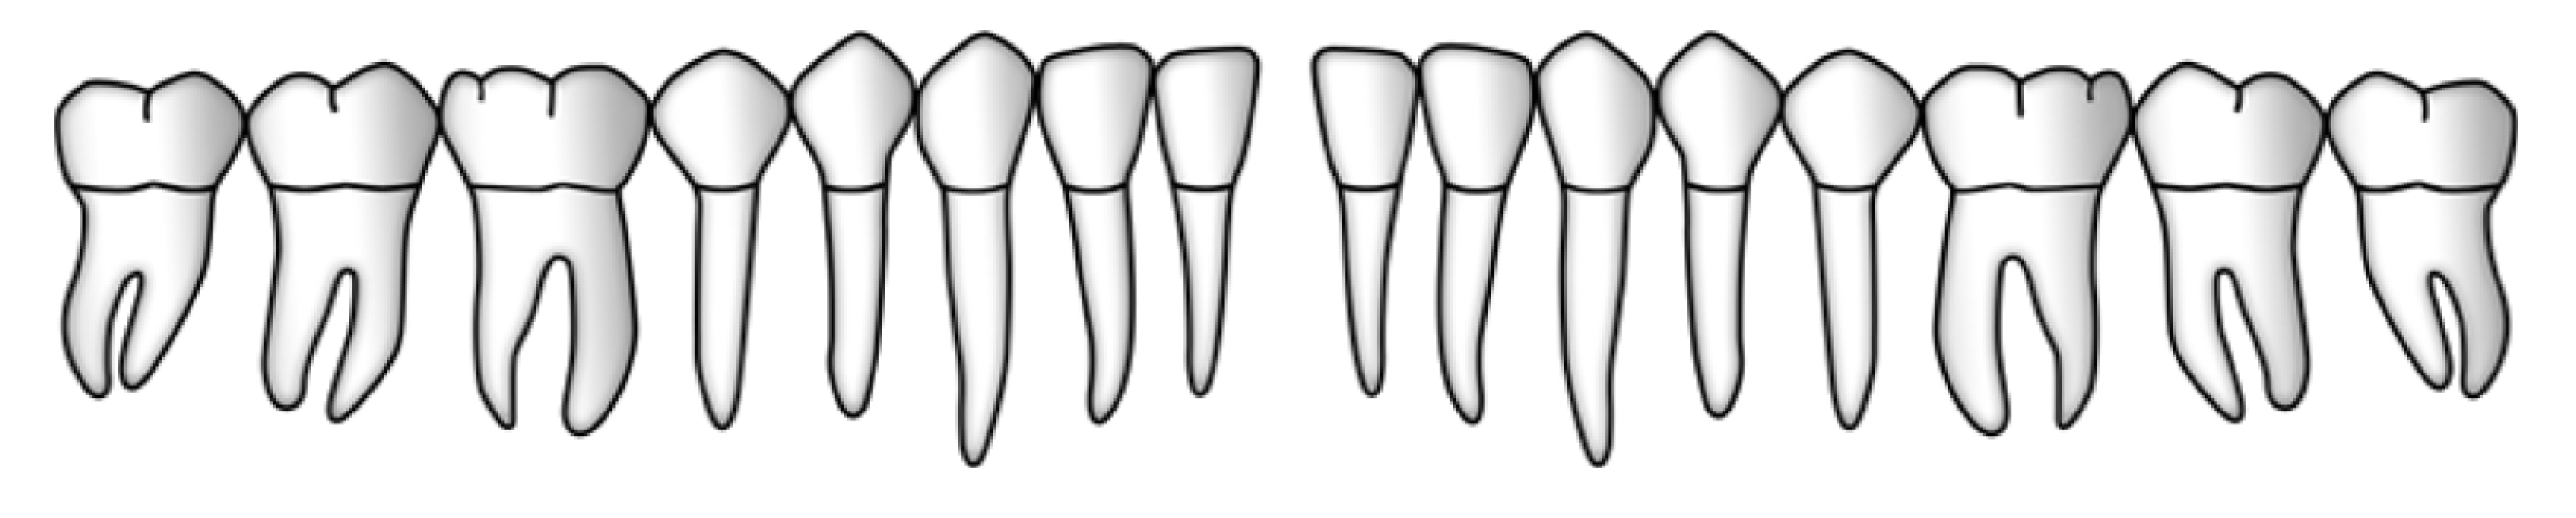

Sechs Messstellen pro Zahn oder Implantat

Entscheidend für die Aufzeichnung sämtlicher parodontalen oder periimplantären Messungen ist die Wahl der richtigen sechs Stellen um den Zahn oder um das Implantat. Hierfür wird der Zahn oder das Implantat von okklusal betrachtet in seinem Umfang in 6 Abschnitte eingeteilt. Für jeden dieser Abschnitte wird die Stelle mit dem höchsten Sondierungswert ermittelt und ausgemessen.

2. Furkationsbefall

Die Furkationen der Molaren sowie der ersten Praemolaren im Oberkiefer werden mit einer Furkationssonde untersucht. Die horizontale Komponente der gesamten Eindringtiefe wird nach folgenden Kriterien in die Grade 0 - 3 eingeteilt (Hamp et al., 1975).

Grad 0 Furkationseingang nicht sondierbar

Grad 1 Furkation sondierbar, horizontaler Sondierungswert ≤3mm

Grad 2 Furkation sondierbar, horizontaler Sondierungswert >3mm

Grad 3 Furkation durchgehend offen